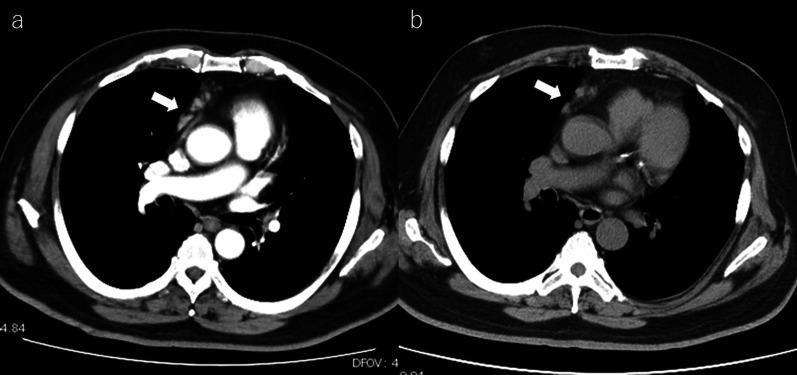

A 66-year-old man with a history of rheumatoid arthritis (RA) was admitted to our department for the treatment of hepatic solitary liver tumor. The patient had been receiving MTX (14 mg/week) for RA for 6 years. MTX was withdrawn and salazosulfapyridine was prescribed 3 weeks prior to admission because of mediastinal MTX-LPD. Abdominal contrast-enhanced computed tomography showed a slightly ring-like enhanced hypovascularized mass (80 mm) in the lateral section of the liver. Carbohydrate antigen 19-9 (78.1 U/mL) level was elevated. No evidence was observed on esophagogastroduodenoscopy or colonoscopy. The tumor was suspected to be an intrahepatic cholangiocarcinoma. The patient underwent hepatic lateral sectionectomy and lymphadenectomy. Pathological examination revealed that the hepatic mass was coagulative necrosis of the CD20-positive B-cell lymphocytes. These histological findings were similar to those of rapid necrotic lymphoma. MTX-LPD is known to spontaneously regress after withdrawing MTX, and the patient was diagnosed with hepatic MTX-LPD.

一名66岁有类风湿关节炎(RA)病史的男性因治疗肝脏孤立性肿瘤入住我科。该患者因RA接受甲氨蝶呤(14mg/周)治疗6年。因纵隔MTX-LPD,在入院前3周停用甲氨蝶呤并开具柳氮磺胺吡啶。腹部增强计算机断层扫描显示肝脏外侧段有一个略呈环状强化的低血运肿块(80mm)。糖类抗原19-9(78.1U/mL)水平升高。食管胃十二指肠镜检查或结肠镜检查未发现异常。肿瘤疑似为肝内胆管癌。患者接受了肝外侧段切除术和淋巴结清扫术。病理检查显示肝脏肿块为CD20阳性B淋巴细胞的凝固性坏死。这些组织学表现与快速坏死性淋巴瘤相似。已知MTX-LPD在停用甲氨蝶呤后可自发消退,该患者被诊断为肝MTX-LPD。